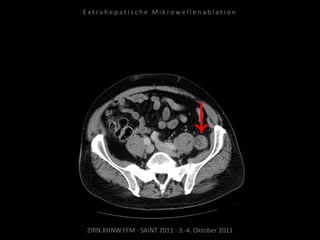

Metastase medial des linken

Musculus iliacus:

1 Nadelposition.

Erneute Ablation von 2 peritonealen

Metastasen am 09.09.2010.